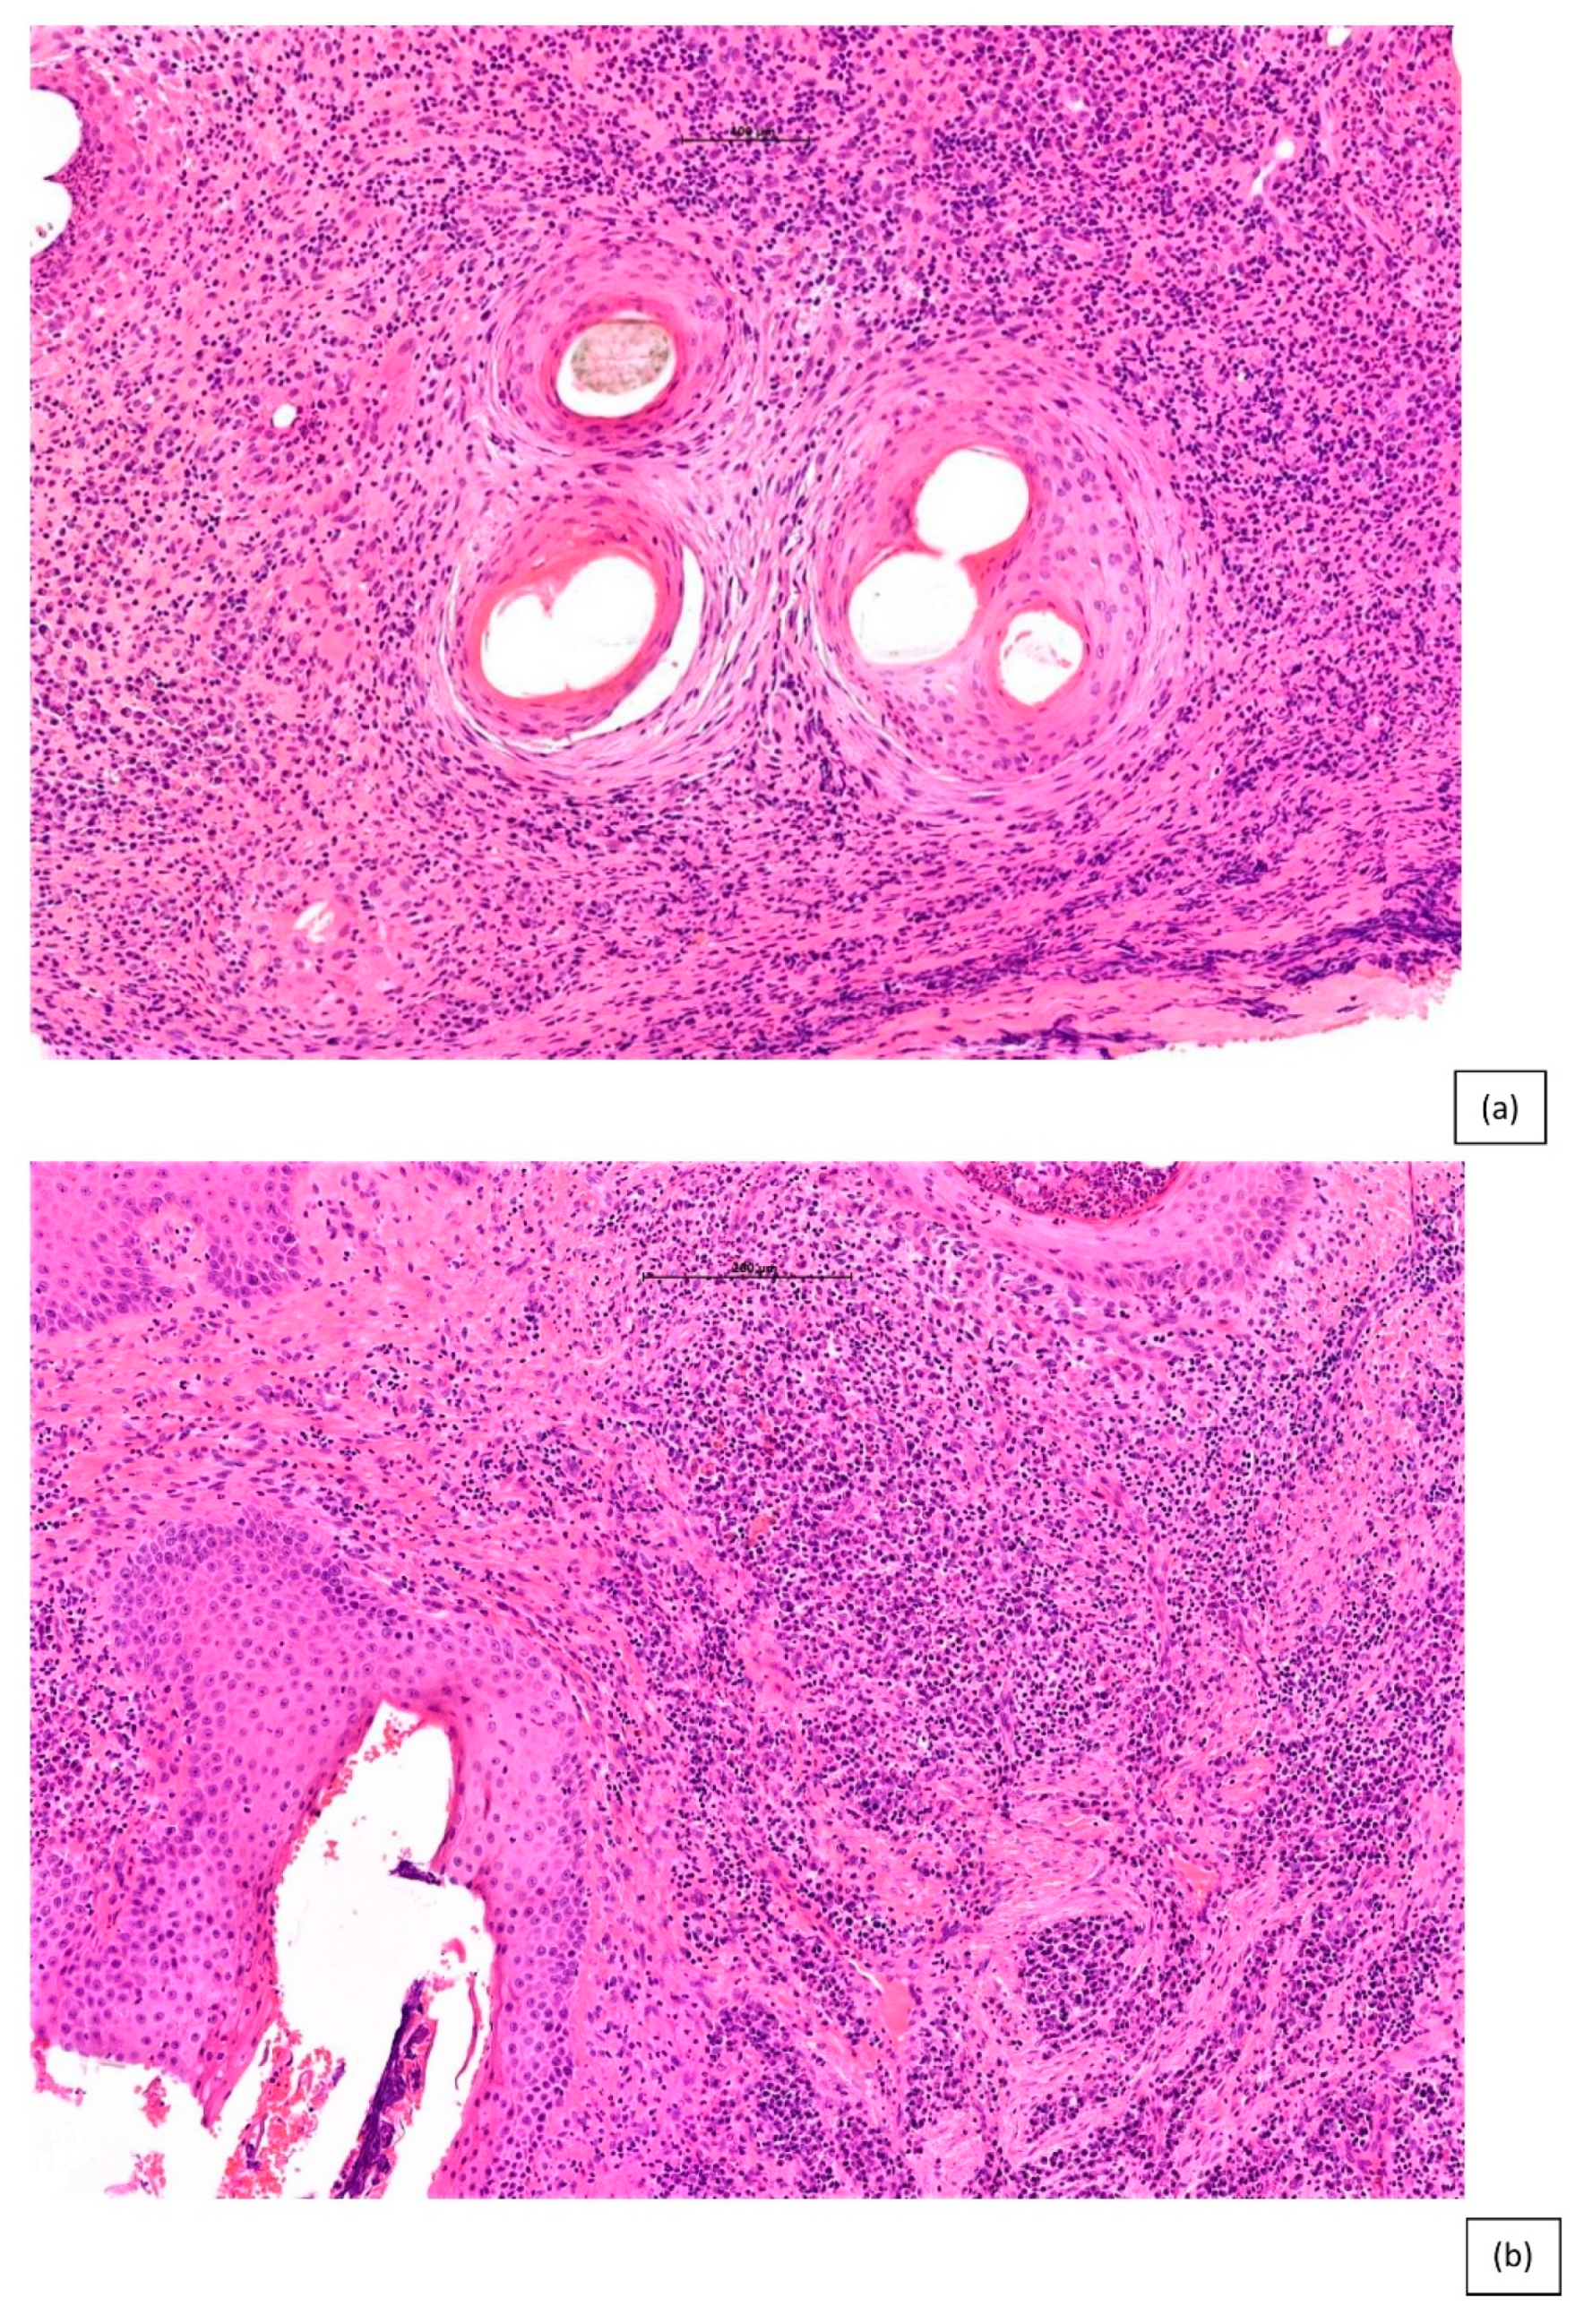

- Miteva, M.; Torres, F.; Tosti, A. The ‘eyes’ or ‘goggles’ as a clue to the histopathological diagnosis of primary lymphocytic cicatricial alopecia. Br. J. Dermatol. 2012, 166, 454–455. [Google Scholar] [CrossRef] [PubMed]

- Miteva, M.; Tosti, A. The follicular triad: A pathological clue to the diagnosis of early frontal fibrosing alopecia. Br. J. Dermatol. 2012, 166, 440–442. [Google Scholar] [CrossRef] [PubMed]

| Epidermis and hair follicle epithelium | Sparing of interfollicular epidermis | Interfollicular epidermal changes (follicular plugging, vacuolar alteration and atrophy) | Eccentric atrophy of the follicular epithelium | Flattened and “squamatisation of hair follicle epithelium surrounded by a zone of fibroplasia and inflammation |

| Inflammation | Perifollicular infiltrates (predominately lymphocytic although histiocytes also occur) with sparing of deep vascular plexus and adnexal structures | Superficial and deep lymphocytic infiltrate involving eccrine glands | Variably dense lymphocytic perifollicular inflammation, primarily at the level of the upper isthmus and lower infundibulum | Predominantly neutrophils, with a component of both lymphocytes and plasma cells at varying depths |

| Distinguishing features | Peri-follicular infundibular lichenoid (band-like) inflammation and apoptotic bodies | Vacuolar interface change Dermal mucin Thickened basement membrane | PDRIS found in early disease and normal appearing scalp | Polytrichia and hair shaft granulomas as a predominant feature |